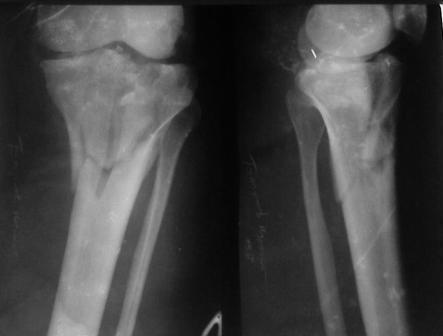

Застарелый перелом 41С3

Обратился больной 46л. 3-месяца назад в каком-то городке Дальнего Востока упал с высоты, сделана Р-графия, наложена гипсовая повязка, от предложенной операции отказался и уехал домой, дальше где и как лечился, не говорит.

Ходит при помощи двух костылей, жалобы на боли при нагрузке, в покое и при движении, без нагрузке боли нет, разгибание 175 гр, сгибание 90 гр, симптомов повреждения связочного аппарата к/с не определяется, от предложенного артродеза пока отказывается.

Уважаемые коллеги! какие будут мнения по поводу лечения, эндопротез недоступен. Заранее благодарю! С уважением Абдурашид.